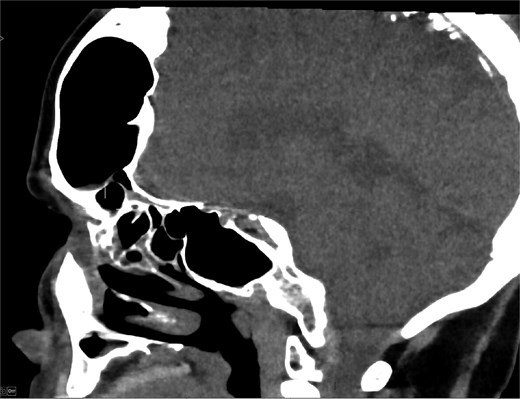

MRI demonstrated marked expansion of the left frontal sinus, consistent with PD, exerting a mass effect on the adjacent left frontal lobe and associated with a small area of increased T2-FLAIR signal intensity (Fig. 1). There was no evidence of compression of the lateral ventricle. However, mild prominence of the sulci and lateral ventricle on the left side suggested underlying parenchymal volume loss. No signs of hydrocephalus, midline shift, restricted diffusion, or susceptibility artifacts were identified. The optic nerve, optic chiasm, and optic tracts appeared normal. CT tomography confirmed these findings (Figs 2 and 3).

CT scan axial view showing hyperaeration of the left frontal sinus.

Coronal CT showing volume loss in the left hemisphere and enlarged sinus.